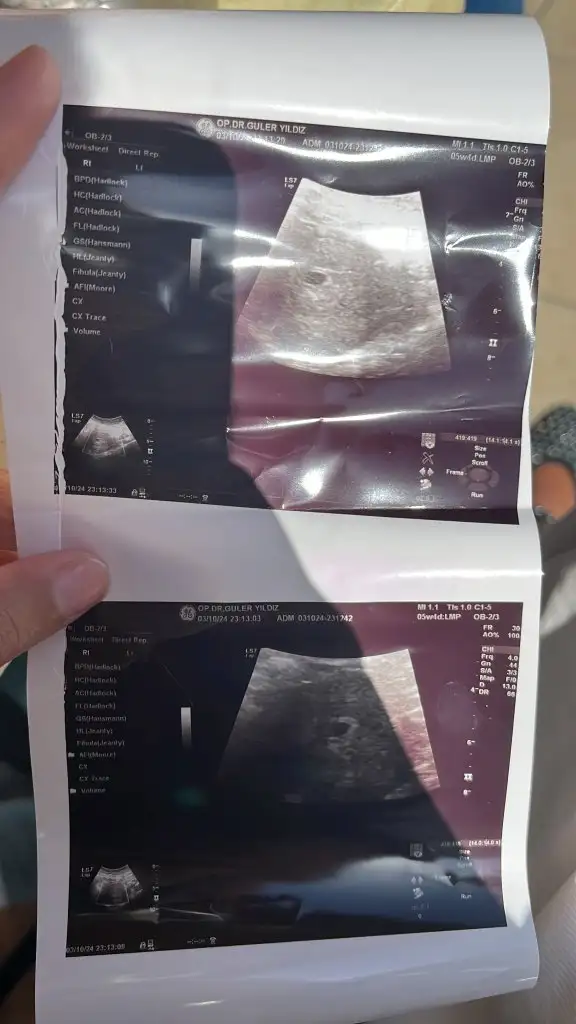

Attım henüz yeni dahaUltrason görüntünüz varsa çok severim yorumlamayı

Erkek benceAttım henüz yeni daha

Fotoğraf da 5+2 sanırım şu an 6+4Kaç haftalık bebişiniz